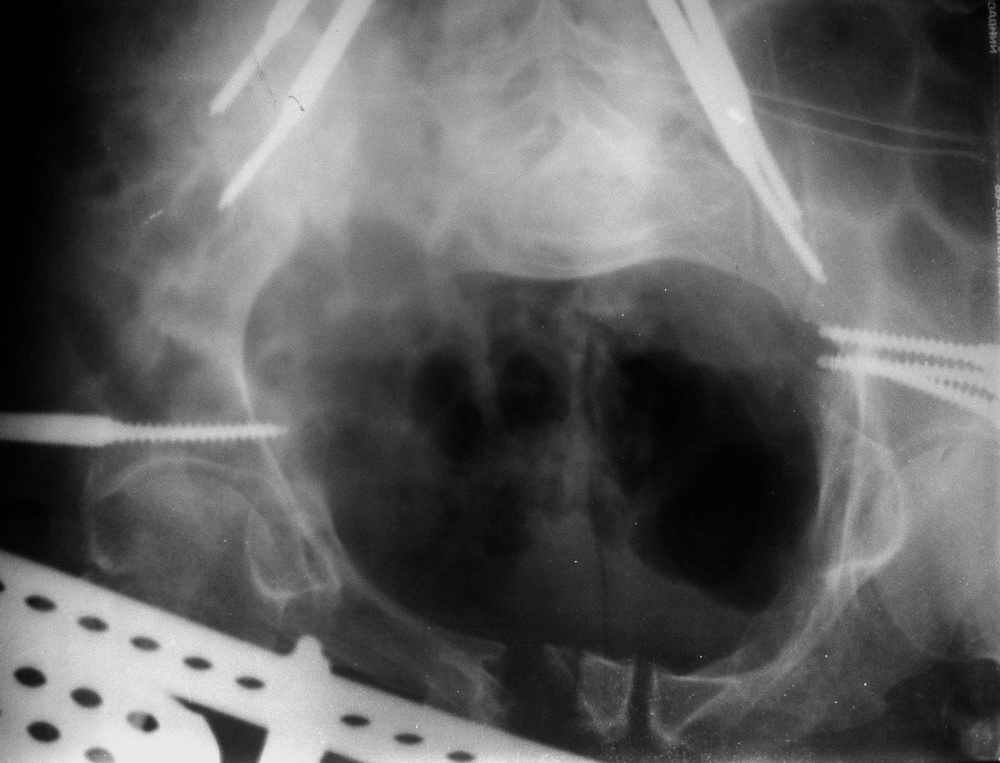

Уважаемые коллеги!Прошу помочь определиться с тактикой лечения пациента 23 лет со сросшимся со смещением вертикальным переломом таза.Заранее благодарю,Виталий Евгеньевич Казеннов, Хабаровск Извлечения из выписного эпикризаБольной Л. М. В., 23 лет, находился на лечении во Взрослом ортопедическом отделении № 2 Краевой больницы № 2 г.Хабаровска с 28 августа 2004 г. по 25 октября 2004 г. с диагнозом: Автотравма 25.07.04 г. Закрытый несвежий осложненный оскольчатый перелом задней колонны и крыши вертлужной впадины справа с задним подвывихом головки бедренной кости. Травматический неврит седалищного нерва справа на уровне тазобедренного сустава с выпадением функции (до пареза) малоберцовой порции. Закрытый вертикальный перелом боковых масс крестца справа со смещением правой половины таза кверху. Срастающийся перелом с/3 правой бедренной кости, фиксированный интрамедуллярно стержнем. Ранний восстановительный период ЗЧМТ.01.09.04 г. Открытая репозиция перелома правой вертлужной впадины, невролиз седалищного нерва, накостный остеосинтез реконструктивной пластиной. Чрескостный остеосинтез костей таза спице-стержневым аппаратом внешней фиксации <таз-бедро>. 25.10.04 Зав. отделением: Сапежников В.А. Врач: Шершнев М.В.

По прямой проекции - Вертикальная стабильная (?) деформация таза IIIст., неправильно сросшийся (?) перелом боковой массы крестца справа, неправильно сросшийся поперечный (?) перелом првавой вертлужной впадины.

Реконструктивная "пластина" очень напоминает трафарет, а не пластину с винтами?! Конгруентность в суставе непонятна.

В любом случае смещение задних отделов более 2-3 см у молодого человека является показанием к его устранениию. План лечения требует данных полипроекционной рентгенографии и кт задних отделов и вертлужной впадины.

Исходная картина